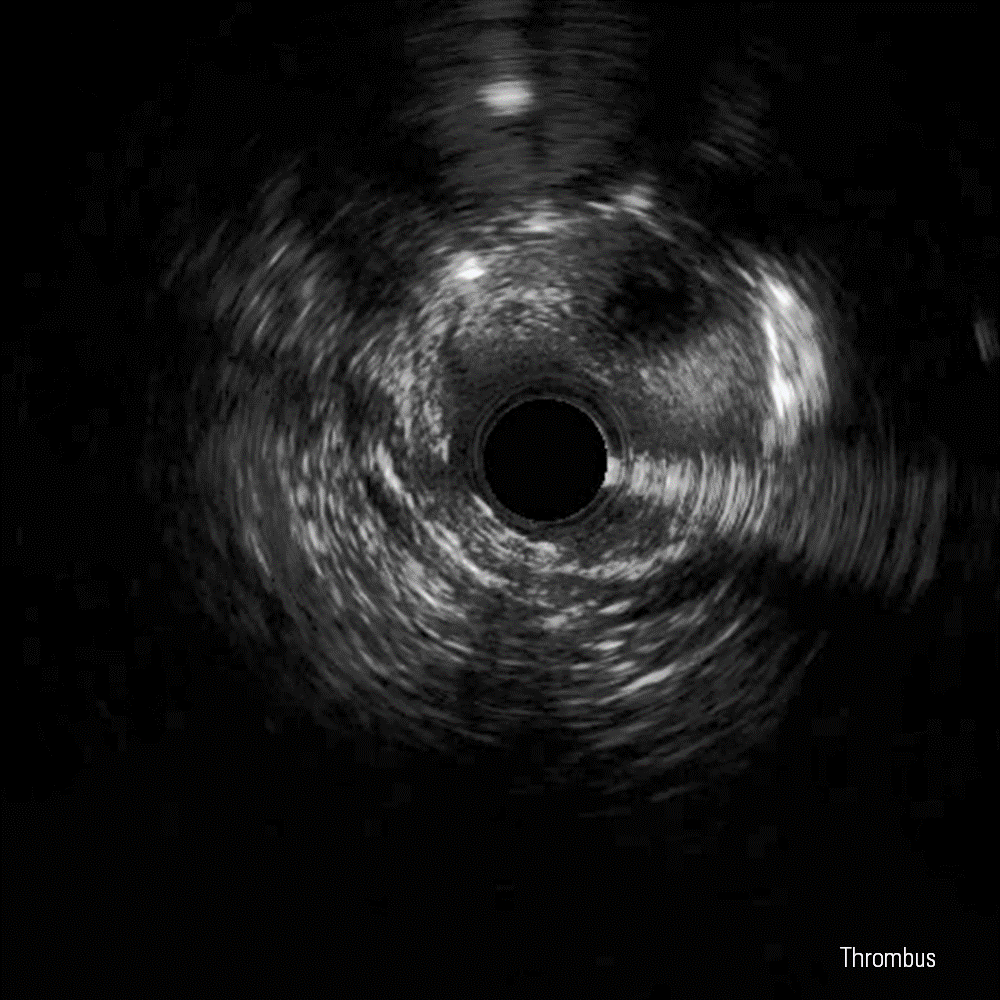

IVUS image for the IVUS image library in Educare

IVUS Image Library

The IVUS image library is a repository of IVUS-guided PCI images including 60 MHz IVUS runs and cross-sectional images, angiograms, and image interpretation tutorials - all available to download.

Dissection, False Lumen and Thrombus images courtesy of Boston Scientific.